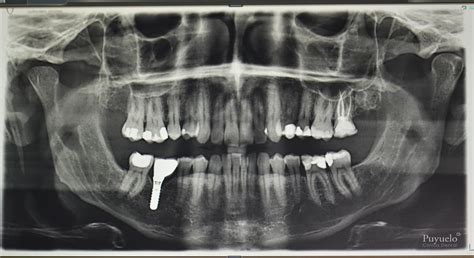

- Planificación de Tratamientos: Es crucial para planificar tratamientos de ortodoncia, implantes y extracciones.

Son las que se toman fuera de la boca. Suelen realizarse con máquinas grandes en salas plomadas dentro de la clínica dental. Sirven para valorar de manera global el conjunto de los dientes, hueso y estructuras. Este tipo de Rx incluye las radiografías panorámicas o ortopantomografías o el TAC Dental 3D (para planificación de implantes dentales).

- Diagnóstico personalizado: uno de nuestros odontólogos estudiará tu caso y, si es necesario, llevará a cabo pruebas adicionales con tecnología avanzada, como escáner intraoral o TAC, para obtener un análisis más preciso.